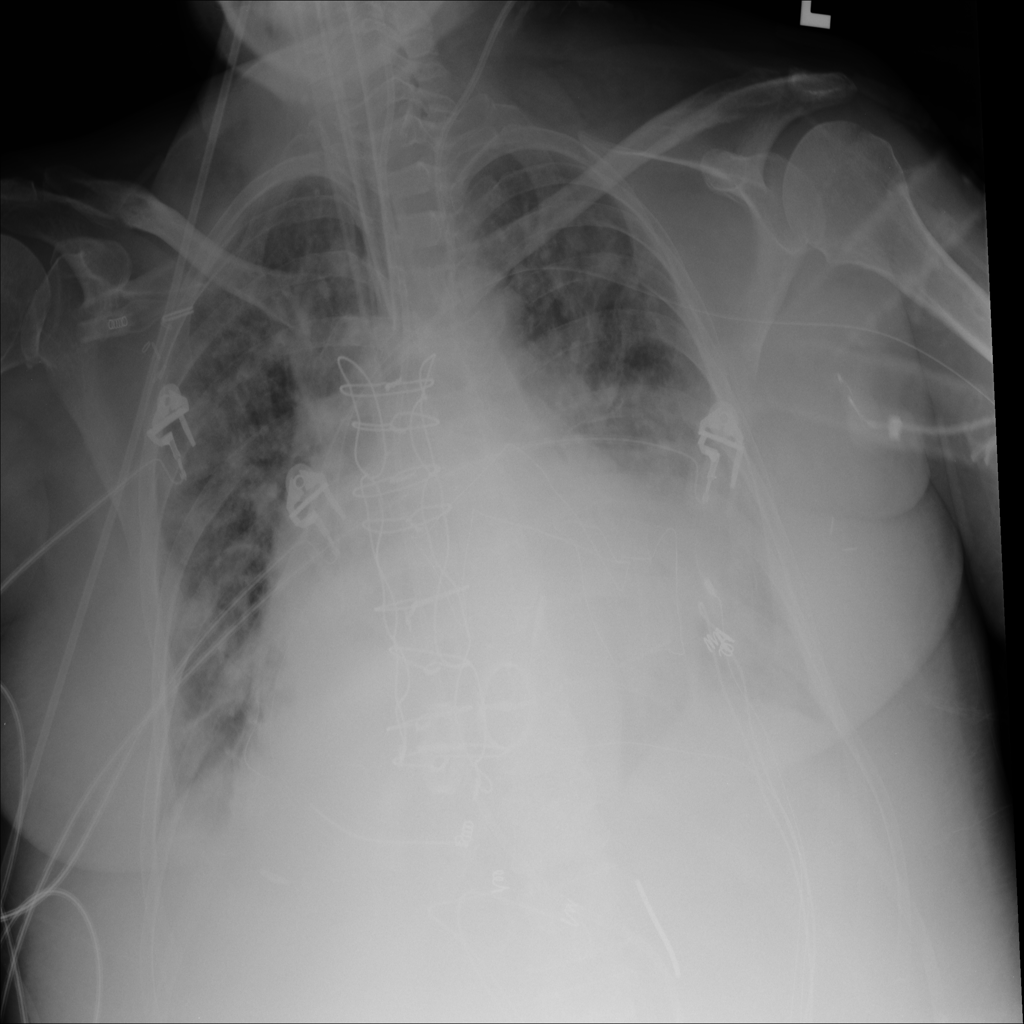

PAT-BA68 · IMG-003Atelectasis

PAT-BA68 · IMG-003

AP